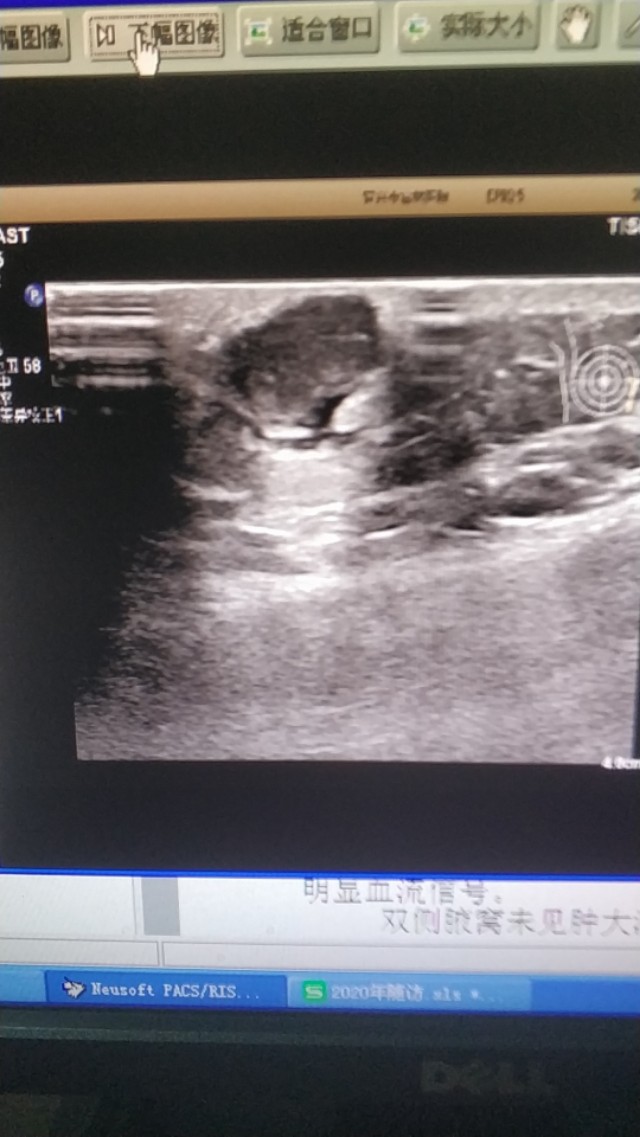

上面是一张胸壁的表皮囊肿,边缘不光滑,下方有液性暗区,这是一个表皮囊肿破裂的病例的。

(这两个病例是上个月随访的)